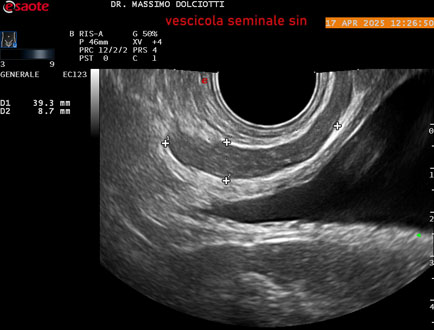

Data inserimento: 01/10/2025

Ecografia del: 17/04/2025

Strumento: Esaote MyLab Eight

Sonda: Convex Multifrequenza 1-8 MHz, Endocavitaria Multifrequenza 3-9 MHz e 3-13 MHz

Età Paziente: M 35 anni

Motivazione dell'esame: disuria.

Commento all'esame: le immagini ed il video documentano la prostata di ecostruttura regolare e morfovolumetria normale con diametro trasversale di 40 mm, diametro anteroposteriore di 21 mm e diametro longitudinale di 43 mm, con volume prostatico calcolato di 18 cc (v.n. < 20 cc), il profilo prostatico è regolare e netto, non si documentano calcificazioni intraghiandolari, la vascolarizzazione della ghiandola è normale. La vescicola seminale destra presenta diametro longitudinale di 44,4 x 7,8 mm, la vescicale seminale sinistra ha diametro longitudinale di 45,3 mm x 7,2 mm.

Conclusioni: prostata normale (normal prostate).